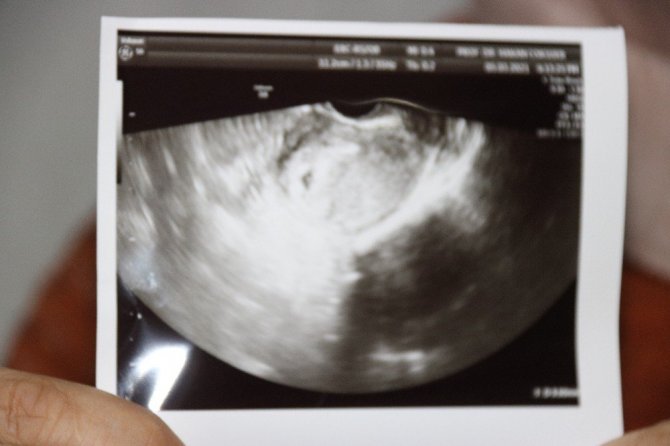

Hastaya daha önce de uygulama yapıldığını ve hiç hücre bulunamadığını belirten Prof. Dr. Hakan Çoksüer, o süreçte tüp bebek uygulamasının da iptal olduğunu söyledi. Prof. Dr. Çoksüer, "Hasta birçok merkezde tedavi almaya çalışmış fakat sperm bulunamadığı için tüp bebek uygulaması yapılamamış. Biz de, hasta kliniğimize geldiğinde ilk önce sperm detoks tedavisi yaptık. Özellikle spermin daha iyi gelişim sağlayabilmesi için. Destoks tedavisinden sonra biz tüp bebek yapmaya karar verdik. Çünkü hastaya baktığımızda hastanın hiç spermi yoktu. Tüp bebek yaptıktan sonra yumurtaları aldığımız esnadan sonra mikro TESE uygulaması yaptık. Mikro TESE'de öncü hücreleri aldıktan sonra Rosi uygulaması yöntemi uyguladık. Rosi yöntemi Japonya'da uygulanmaya başlanmış. Artık son yıllarda bizim ülkemizde yapılıyor. Biz de kendi kliniğimizde Rosi yöntemiyle tüp bebek uygulaması yaptık. Rosi yöntemi sonrası gebelik elde ettik. Tabi bu esnada hastamızın stresi fazla olduğu için biz akupunktur tedavisi yaptık. Akupunkturla hem stresi azalttık hem yumurta kalitesini artırdık. Sonrasında biz transferimizi gerçekleştirdik. Embriyoların gelişimi iyi oldu ve embriyolarımız beşinci güne kadar gitti. Çünkü burada embriyoların da kaliteli olması bizim açımızdan önemli. Transfer sonrası sonucumuzu aldık. 12'nci günde de test yaptığımızda test sonucu pozitifti. Bugün de ultrasona baktığımızda gebelik kesesi gördük. Gebelik kesesini gördükten sonra hasta gözlerine inanamadı. Çünkü hastaya daha önce, hiç hücre olmadığı için imkansız olduğu söylenmiş. Doğru tedavi, doğru merkez, doğru uygulama başaranın ana anahtarıdır" dedi.